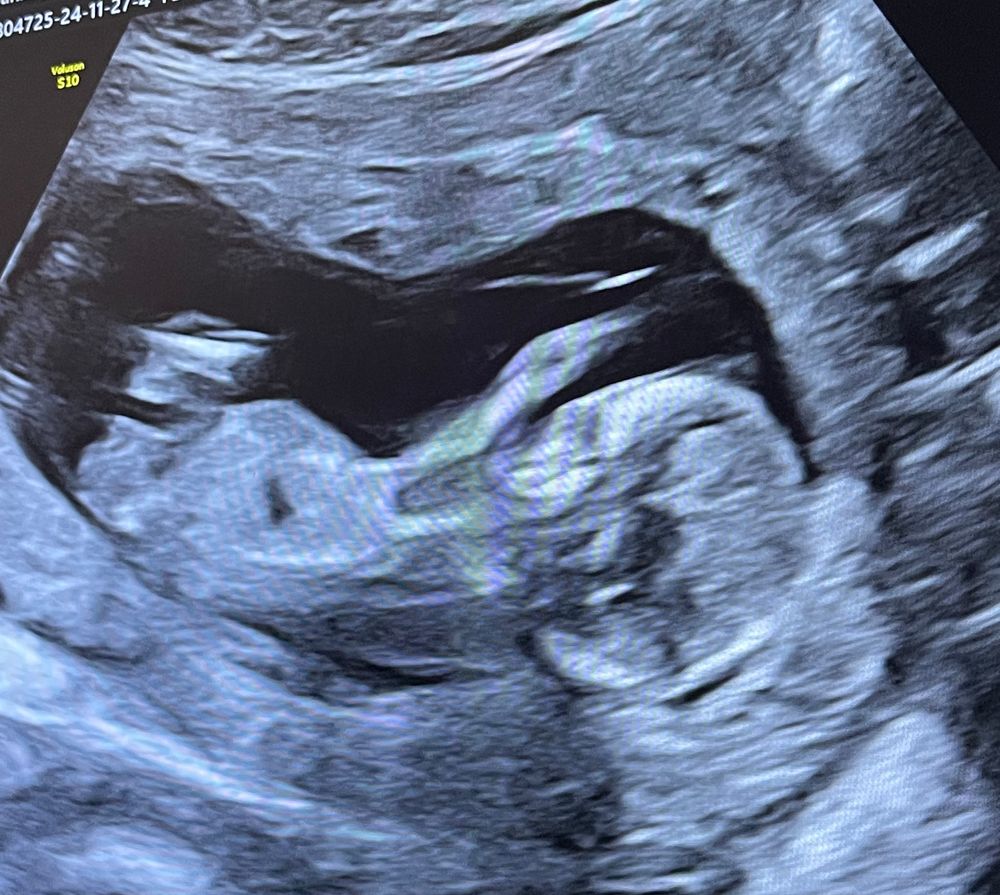

На первом фото половой бугорок не ровно горизонтальный, что говорит о том, что это может быть и мальчик, еще и расположение его мочевого пузыря. А на втором малыш повернулся чуть и кажется буговорок уже ровно горизонтальным. У меня также было, только одно фото было как у вас 1-ое. Узист говорил 50/50 и в итоге жду мальчика💙 Срок еще маленький у вас чтобы 100% говорить пол ребенка, да и половой бугорок еще может измениться. Так что сделайте узи на сроке 17-20 недель

08.12.2024